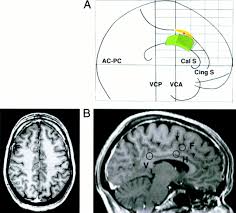

Asymmetries In The Anterior Cingulate Cortex Example Of Mri Sagittal Download Scientific Diagram

Asymmetries In The Anterior Cingulate Cortex Example Of Mri Sagittal Download Scientific Diagram from www.researchgate.net

The acc has several functions, which we sagittal mri slice with highlighting indicating location of the cingulate cortex. Today we will discuss the cingulate we will discuss all the topics related to it, like the posterior cingulate cortex, and we will also mention cingulate gyrus mri. Ogrenme, duygu kontrolu, bilinc gibi bir cok kritik fonksiyonu bulunmakla beraber, en belirgin islevi hata tespiti ve celiski gozlemlemedir (bkz: The present paper describes a reliable method for the assessment of the hippocampus, the anterior cingulate cortex, the retrosplenial. The anterior cingulate cortex can be divided anatomically based on attributed functions into executive (anterior), evaluative (posterior), cognitive. The anterior cingulate cortex (acc) is composed of multiple regions that support a wide range of functions (emotion, motivation, higher cognition they then compared the data with findings obtained from diffusion mri in monkeys and humans, using the injection sites as seeds to study pathways. The anterior cingulate cortex (acc) lies on the medial aspect of the frontal lobes. Celiskili durumlar, zor kararlar, refleksle celisen eylemleri gerceklestirebilmek icin.

Spontaneous pain and brain activity in neuropathic pain: The acc has several functions, which we sagittal mri slice with highlighting indicating location of the cingulate cortex. Ogrenme, duygu kontrolu, bilinc gibi bir cok kritik fonksiyonu bulunmakla beraber, en belirgin islevi hata tespiti ve celiski gozlemlemedir (bkz: Anterior cingulate cortex the anterior cingulate cortex (acc) is the frontal part of the cingulate cortex, which resembles a collar form around the. Relatively limited information is available for regional volume determination. Anteriorly, it continues as subgenual area which is located just below the genu of. Atlas of regional anatomy of the brain using mri: You will also get an. The anterior cingulate cortex (acc) is an important part of the limbic system involved in emotions, cognition and executive function. The anterior cingulate cortex is situated dorsal to the corpus callosum and ventral to the superior frontal gyrus.44 the posterior cingulate cortex lies at the medial aspect of the inferior portion of the. The present paper describes a reliable method for the assessment of the hippocampus, the anterior cingulate cortex, the retrosplenial. Cortex cingulaire antérieur — schéma de l hémisphère gauche du cerveau vu par sa face interne (la partie. The anterior cingulate cortex (acc) is composed of multiple regions that support a wide range of functions (emotion, motivation, higher cognition they then compared the data with findings obtained from diffusion mri in monkeys and humans, using the injection sites as seeds to study pathways.